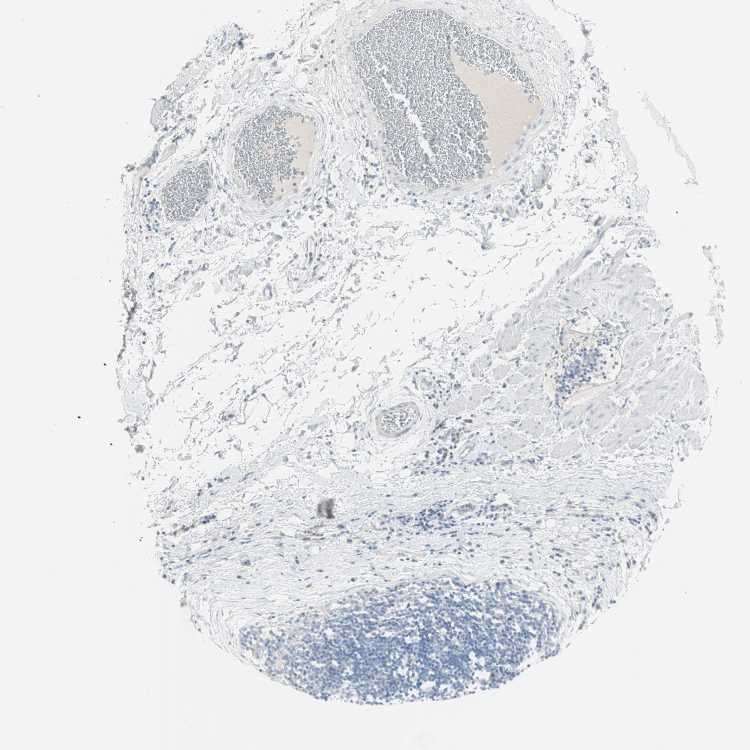

SOFT TISSUE 1 - Antibody stainingi

Antibody staining in the annotated cell types in the current human tissue is reported as not detected, low, medium, or high, based on conventional immunohistochemistry profiling in selected tissues. This score is based on the combination of the staining intensity and fraction of stained cells.

Each image is clickable and will lead to virtual microscopy that enables deeper exploration of all samples and also displays staining intensity scores, fraction scores and subcellular localization as well as patient and tissue information for each sample.

Antibody HPA009081Antibody HPA009173Antibody CAB025004

Chondrocytes HighNot detected-

Fibroblasts Not detectedLowNot detected

Peripheral nerve --Not detected